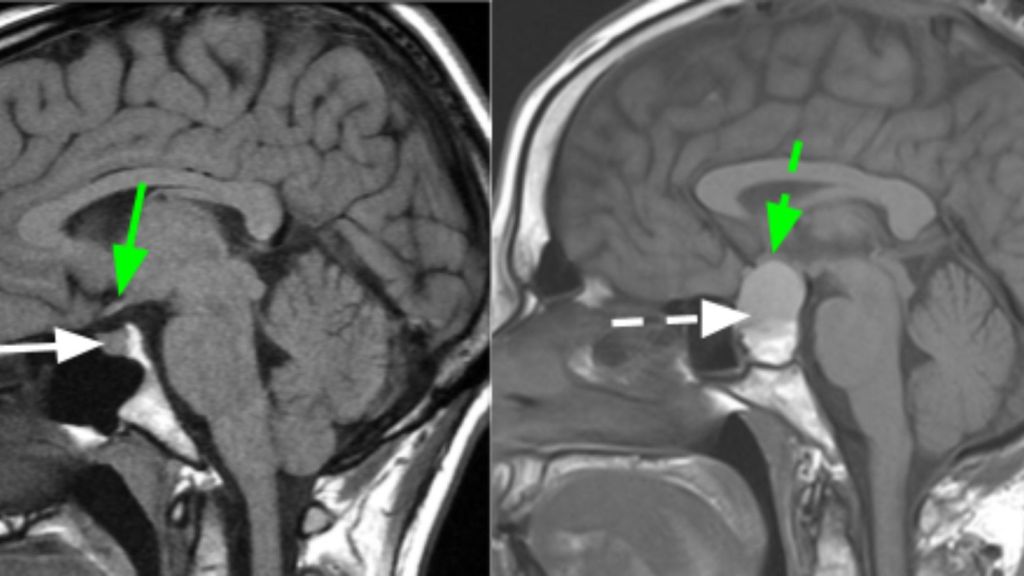

Në bazë të madhësisë, ato klasifikohen në mikroadenoma, makroadenoma dhe tumore gjigante. Mikroadenoma është një tumor më pak se 10 mm, ndërsa makroadenoma përshkruan një tumor më të madh se 10 mm. Tumoret gjigante të hipofizës janë më të mëdha se 40 mm.

Në rast dyshimi për adenomë të hipofizës, ekazminmiet specifike përfshijnë vlerësimin hormonal dhe ekzaminim imazherik (rezonance magnetike me kontrast intravenoz). Vlerësimi përfshin matjen e hormoneve të ndryshme si prolaktina, TSH, T4 e lirë, hormoni folikul-stimulues (FSH), IGF-1, GH, ACTH, estradioli, testosteroni, BMP dhe kortizoli në mëngjes herët në mëngjes. Në varësi të gjetjeve të para, shtohen ekzaminime të tjera të nevojshme për të gjykuar mbi planin terapeutik.